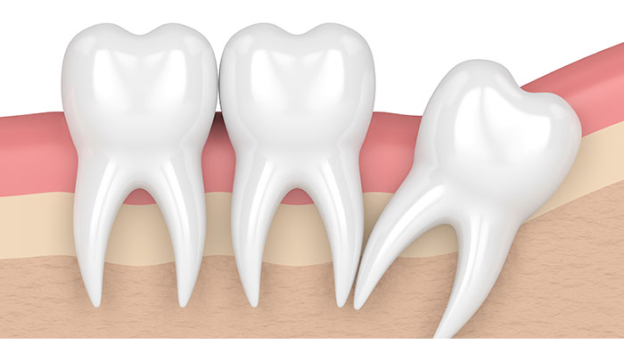

• 사랑니 발치 이유 3

삐뚤어져 나는 사랑니

사랑니가 삐뚤게 자라면 주변 치아의 뿌리를 녹이거나 인접한 면에 음식물이 잘 끼게 되어 충치가 생길 수 있습니다.

• 사랑니 발치 이유 4

옆으로 누워서 자란 사랑니

사랑니가 누워서 자라면 바로 앞쪽 어금니 뿌리를 압박해 염증 등의 문제를 일으키거나 앞쪽 어금니와의 사이에 음식물이 잘 끼게 되어 충치와 염증을 유발할 수 있습니다.